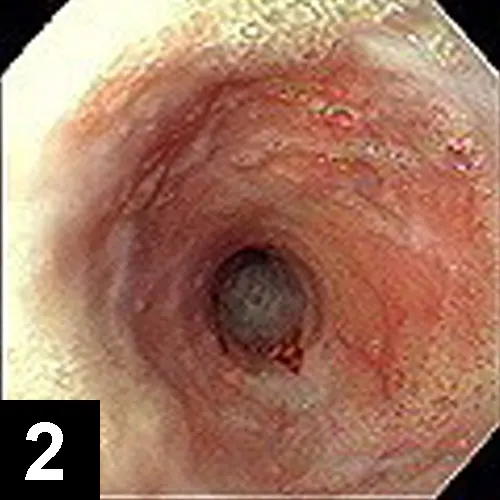

The most likely cause of this abnormality is an intramural esophageal stricture. Unlikely causes for esophageal narrowing include extrinsic extraesophageal compression from neoplasia or inflammation, vascular ring anomaly, presence of an esophageal foreign body, or esophageal neoplasia. Endoscopy was done to delineate the obstruction and to perform therapeutic esophageal dilatation. Figure 2 shows the esophageal narrowing at the thoracic inlet. Figure 3 shows the esophagus following a balloon dilatation procedure.

Figure 2. Endoscopic view showing a benign focal esophageal stricture secondary to a doxycycline tablet in a cat